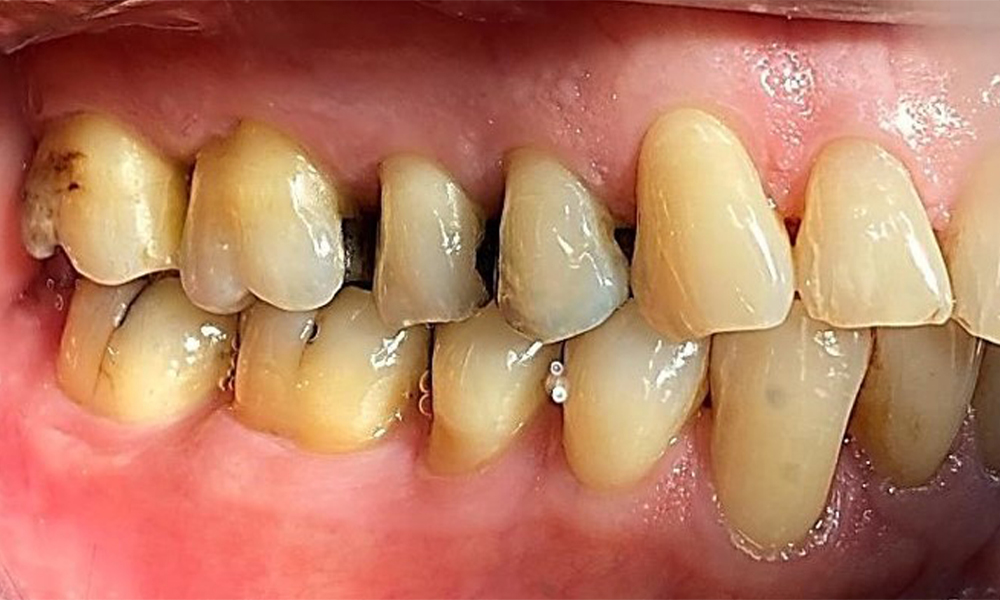

The patient has a full dentition with 28 teeth, which includes amalgam and composite fillings in the molar and premolar regions. There is a visible clinical marginal gap present on tooth 14. Tooth 27 has an adequate gold inlay. There are also generalized attritions and abrasions. (Fig. 2, Fig. 3, Fig. 4, Fig. 5, Fig. 6)

The patient has stage II, grade B periodontitis (5). At 1 to 3 mm, the clinical probing depths were within the physiological range. Localized probing depths of 5 mm were observed on the mesiopalatal aspects on both 17 and 27. There are generalized recessions of 1–3 mm with partial loss of the interdental papillae (Fig. 2, Fig. 3, Fig. 4)